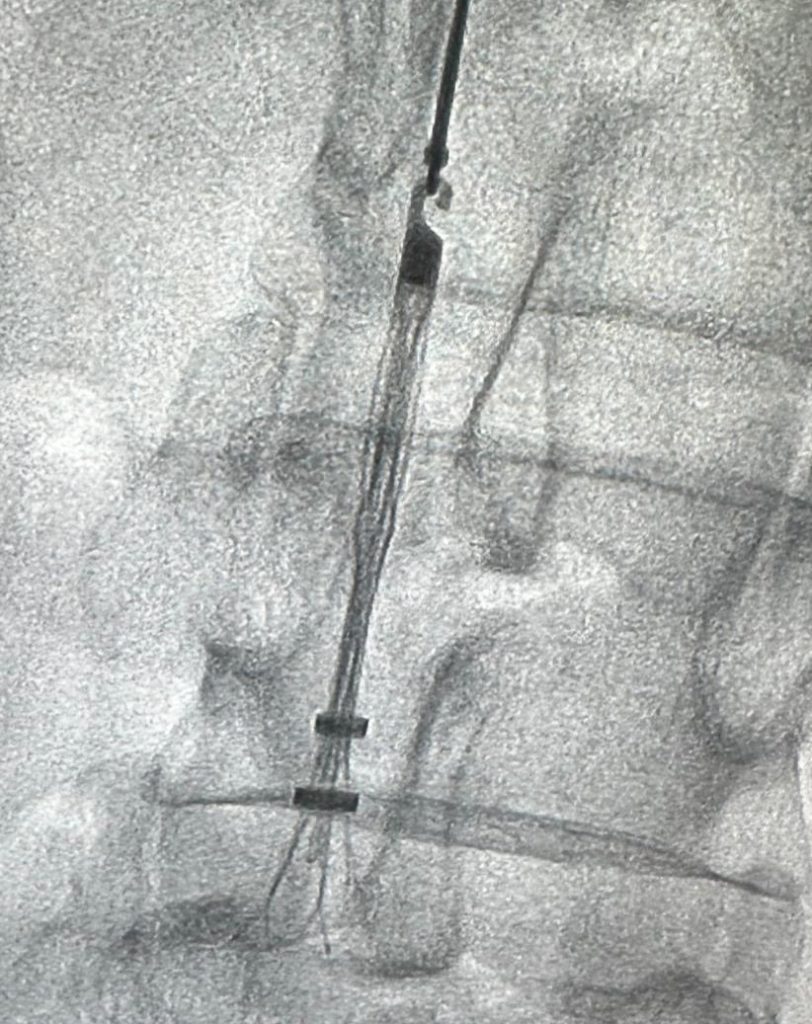

Filter IVC, juga dikenal sebagai filter vena cava inferior, adalah perangkat medis kecil yang ditanamkan di vena cava inferior, yaitu vena besar yang membawa darah terdeoksigenasi dari tubuh bagian bawah kembali ke jantung. Tujuan dari filter IVC adalah untuk menangkap bekuan darah yang mungkin terbentuk di kaki sebelum mencapai paru-paru dan menyebabkan kondisi yang berpotensi mengancam jiwa yang disebut emboli paru. Biasanya digunakan pada pasien yang berisiko tinggi mengalami penggumpalan darah namun tidak dapat mengonsumsi obat antikoagulan atau mengalami komplikasi.

Di sisi lain, filter IVC yang dapat diambil dirancang untuk ditempatkan sementara di vena cava untuk mencegah penggumpalan darah dan kemudian dilepas setelah risiko penggumpalan berkurang. Filter ini sering digunakan dalam situasi di mana risiko penggumpalan darah pada seseorang bersifat sementara, seperti setelah operasi atau trauma. Proses pengambilan biasanya dilakukan dengan prosedur invasif minimal, biasanya melalui leher atau selangkangan, dan dapat dilakukan dalam sehari dengan obat penenang dan anestesi lokal.